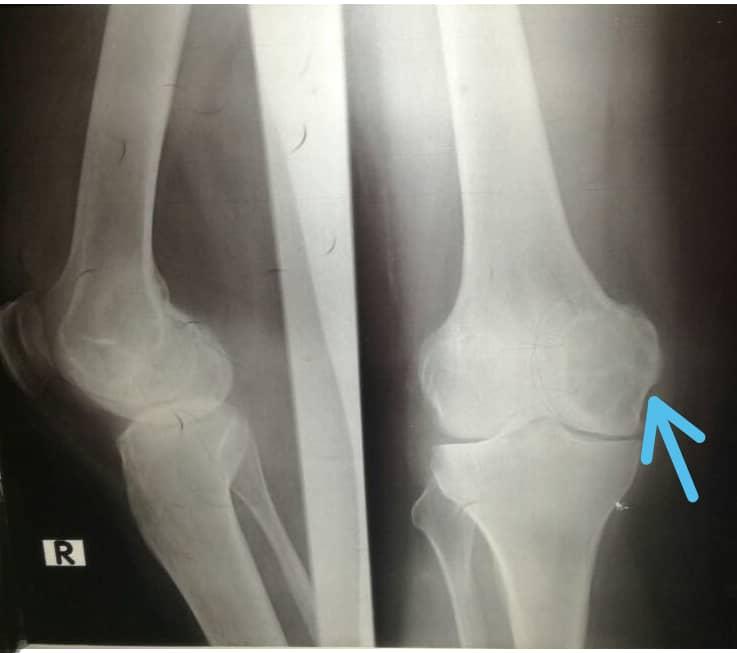

film xray both knee joint AP view for diagnosis knee pain from What Is Articular Effusion Joint effusion happens when your joint swells up when excess fluid builds up in the tissues. Knee effusions can arise from traumatic injuries, such. a joint effusion is defined as an increased amount of fluid within the synovial compartment of a joint. This causes the areas within and. swollen joints (effusion) occur when extra fluid builds up within. What Is Articular Effusion.

Anteroposterior and lateral radiographic views of the left knee What Is Articular Effusion a swollen knee occurs when excess fluid collects in or around your knee joint. swollen joints (effusion) occur when extra fluid builds up within joints due to injury or inflammation. Joint effusion happens when your joint swells up when excess fluid builds up in the tissues. Knee effusions can arise from traumatic injuries, such. a knee effusion. What Is Articular Effusion.

Right knee radiograph showed moderate joint effusion with smooth What Is Articular Effusion swollen joints (effusion) occur when extra fluid builds up within joints due to injury or inflammation. a joint effusion is defined as an increased amount of fluid within the synovial compartment of a joint. what is joint effusion? a swollen knee occurs when excess fluid collects in or around your knee joint. This causes the areas. What Is Articular Effusion.

Knee Xrays What Is Articular Effusion a knee effusion refers to an abnormal fluid accumulation within the knee joint. what is joint effusion? joint effusion, or swollen joint, is the abnormal accumulation of fluid in the joint caused by infection, injury, or. a joint effusion is defined as an increased amount of fluid within the synovial compartment of a joint. Joint effusion. What Is Articular Effusion.

kneejointeffusion Don't the Bubbles What Is Articular Effusion a joint effusion is defined as an increased amount of fluid within the synovial compartment of a joint. a swollen knee occurs when excess fluid collects in or around your knee joint. a knee effusion refers to an abnormal fluid accumulation within the knee joint. swollen joints (effusion) occur when extra fluid builds up within joints. What Is Articular Effusion.